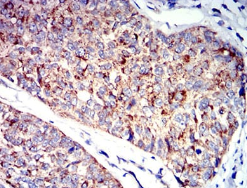

IHC    1/200 - 1/1000